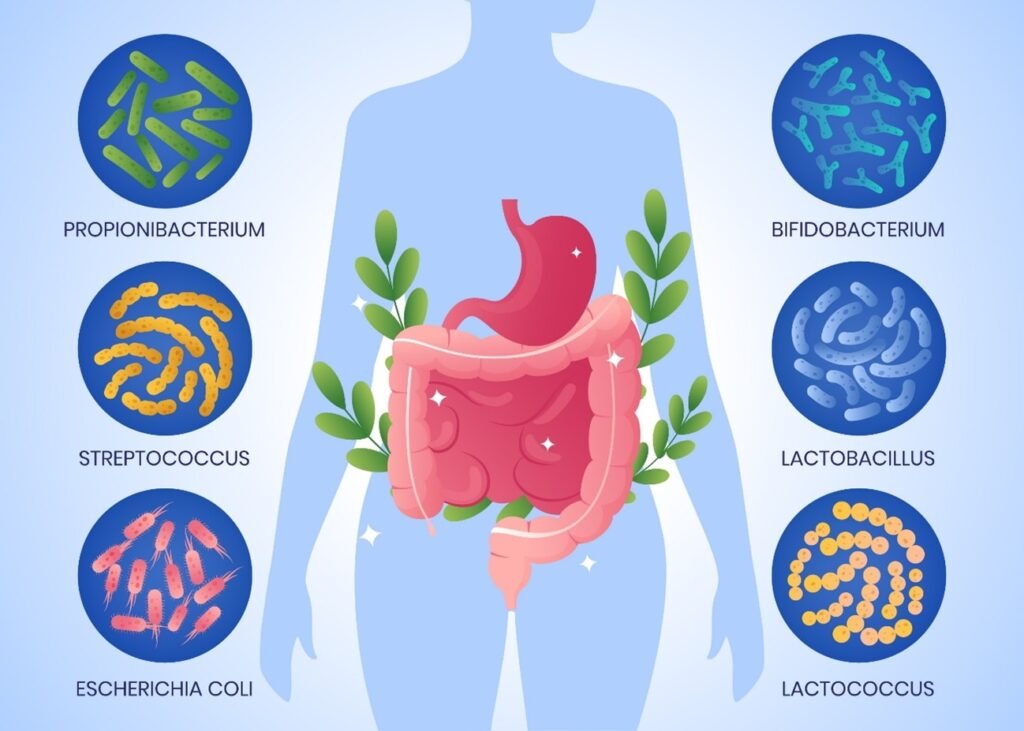

- Oral Microbiome: The ecosystem of microorganisms in the mouth plays a role in oral health. Body shifts of this balance can result in dental caries (cavities) and gum diseases like gingivitis and periodontitis.